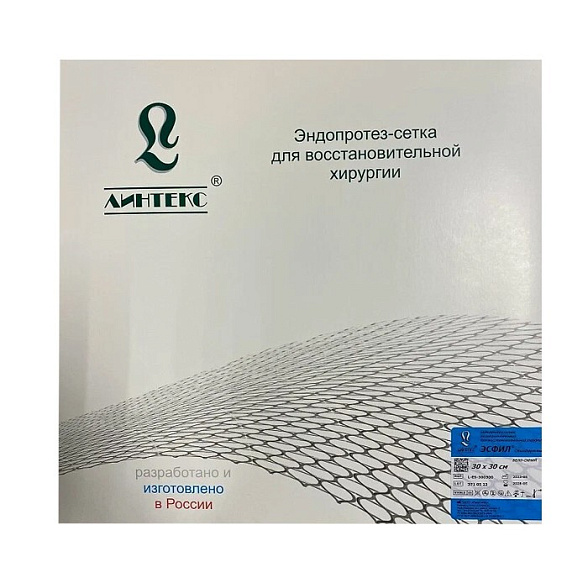

Эндопротез-сетка (сетка хирургическая) полипропиленовый для восстановительной хирургии ЭСФИЛ тяжелый, 6х11 см, Линтекс

Эндопротез-сетка полипропиленовая ЭСФИЛ тяжелый для восстановительной хирургии

Полипропиленовая хирургическая сетка ЭСФИЛ тяжелый от компании «Линтекс» — это современный высокотехнологичный имплантат, предназначенный для надежного и долговечного укрепления тканей в ходе сложных реконструктивных операций. Изделие специально разработано для ситуаций, требующих повышенной механической прочности и стабильности.

| Наименование товара | Эндопротез-сетка хирургическая полипропиленовая |

| Торговое название / Модель | ЭСФИЛ тяжелый (ESFIL Heavy) |

| Бренд / Производитель | Линтекс (Lintex) |

| Страна изготовления | Россия |

| Размер | 6 см x 11 см |

| Стерильность | Стерильно, индивидуальная упаковка |